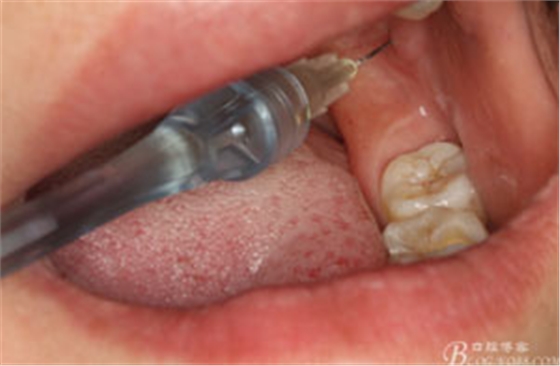

圖4.行下頜無痛阻滯麻醉